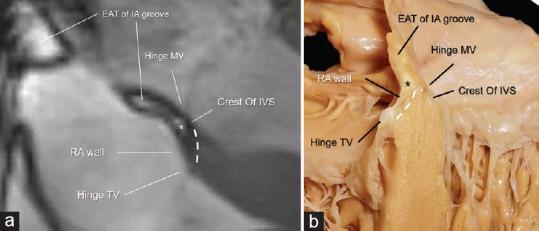

The epicardial adipose tissue (EAT) refers to the deposition of adipose tissue fully enclosed by the pericardial sac. EAT has a complex mixture of adipocytes, nervous tissue, as well as inflammatory, stromal and immune cells secreting bioactive molecules. This heterogeneous composition reveals that it is not a simply fat storage depot, but rather a biologically active organ that appears playing a "dichotomous" role, either protective or proinflammatory and proatherogenic. The cardiac magnetic resonance (CMR) allows a clear visualization of EAT using a specific pulse sequence called steady-state free precession. When abundant, the EAT assumes a pervasive presence not only covering the entire epicardial surface but also invading spaces that usually are almost virtual and separating walls that usually are so close each other to resemble a single wall. To the best of our knowledge, this aspect of cardiac anatomy has never been described before. In this pictorial review, we therefore focus our attention on certain cardiac areas in which EAT, when abundant, is particularly intrusive. In particular, we describe the presence of EAT into: (a) the interatrial groove, the atrioventricular septum, and the inferior pyramidal space, (b) the left lateral ridge, (c) the atrioventricular grooves, and (d) the transverse pericardial sinus. To confirm the reliability in depicting the EAT distribution, we present CMR images side-by-side with corresponding anatomic specimens.

心外膜脂肪组织(EAT)是指被心包囊完全包裹的脂肪组织沉积。EAT由脂肪细胞、神经组织以及分泌生物活性分子的炎症细胞、基质细胞和免疫细胞混合而成。这种异质性组成表明它并非简单的脂肪储存库,而是一个具有生物活性的器官,似乎发挥着“双重”作用,既有保护作用,也有促炎和促动脉粥样硬化作用。心脏磁共振成像(CMR)使用一种称为稳态自由进动的特定脉冲序列能够清晰显示EAT。当EAT大量存在时,它不仅会遍布整个心外膜表面,还会侵入通常几乎是虚拟的空间,并分隔通常彼此靠近而看似单一壁的壁。据我们所知,心脏解剖学的这一方面以前从未被描述过。因此,在这篇图片综述中,我们将注意力集中在某些心脏区域,当EAT大量存在时,这些区域的EAT特别具有侵入性。具体来说,我们描述了EAT在以下部位的存在情况:(a)房间沟、房室间隔和下锥体间隙,(b)左侧嵴,(c)房室沟,以及(d)心包横窦。为了证实描绘EAT分布的可靠性,我们将CMR图像与相应的解剖标本并排展示。